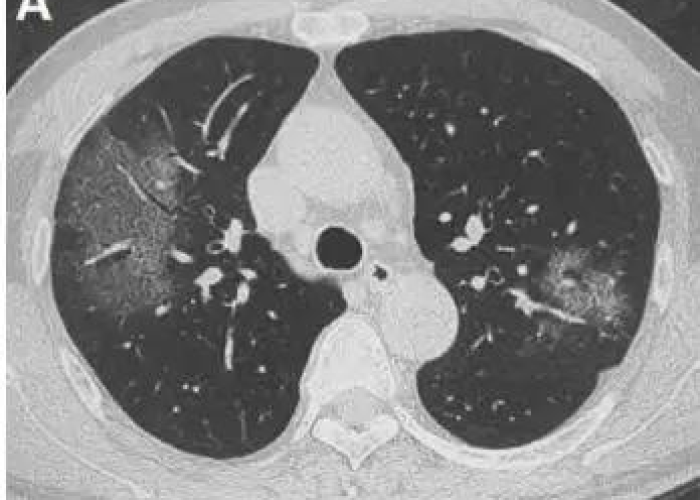

贰→ 新型冠状病毒感染有可能自愈,但需分情况讨论。 轻症患者自愈可能性较高对于仅出现低热、头晕、鼻塞、轻微乏力等症状,且无继发性肺炎表现的轻症患者,其免疫系统可能通过自身防御机制清除病毒。

叁→ 目前新型冠状病毒感染的治疗主要包括以下几个方面:一般治疗隔离与监测:确诊患者需隔离治疗以阻断传播,同时密切监测生命体征(如体温、呼吸、心率、血压)、血氧饱和度、血常规、生化指标及凝血功能,评估病情进展。支持治疗:保证能量摄入,维持水、电解质平衡,补充维生素及微量元素。